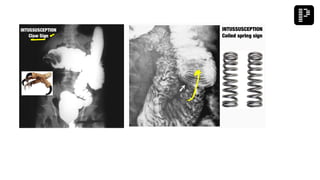

Q. A multipara patient was brought to the emergency with signs and symptoms of small bowel

obstruction. After resuscitation, X-ray was performed and the findings are given below.

What is the most probable diagnosis?